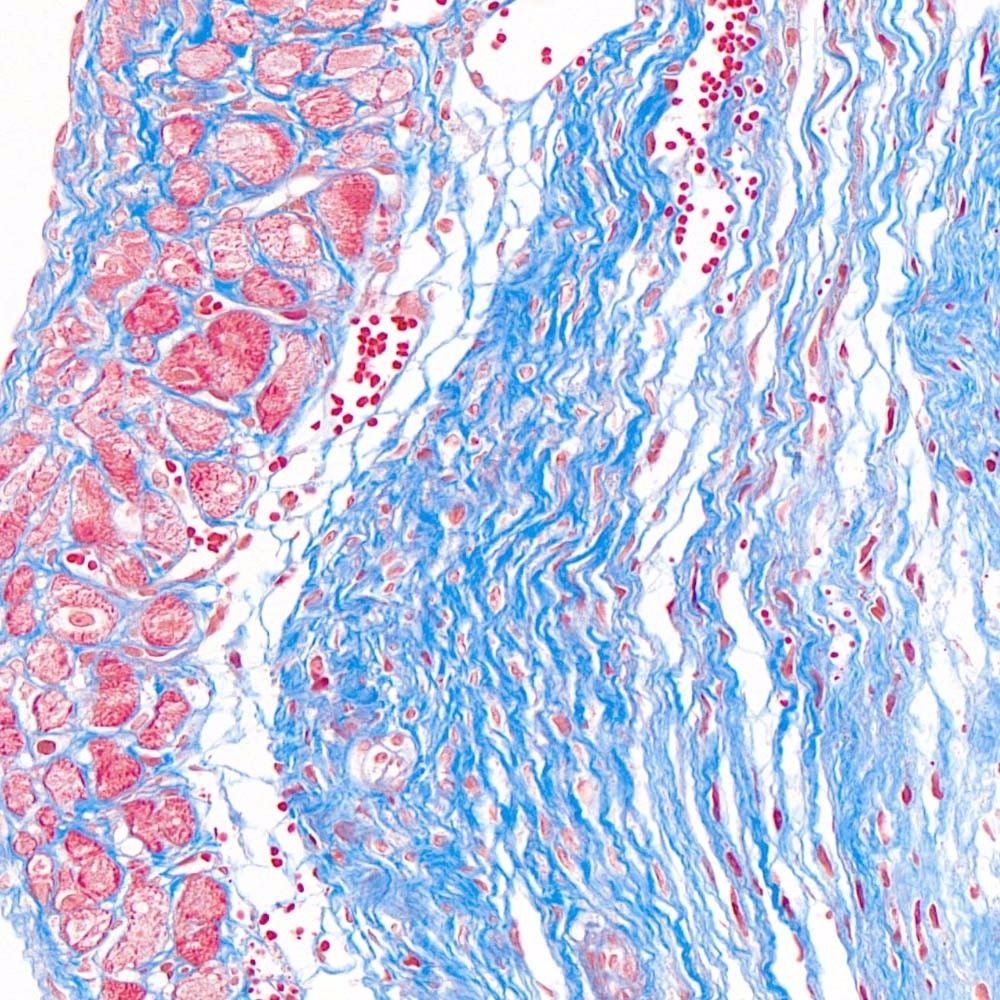

首先,讓我們深入探討MASSON染色的原理。MASSON染色的原理與陰離子染料分子的大小和組織的滲透性密切相關(guān)。染料的分子量決定了其穿透組織的能力:小分子量的染料更容易穿透結(jié)構(gòu)致密、滲透性較低的組織,而大分子量的染料則更傾向于進入結(jié)構(gòu)疏松、滲透性較高的組織。在MASSON染色中,由于肌纖維間隙較小,而膠原纖維間隙較大,因此小分子量的麗春紅染料更容易滲透進入肌纖維并使其呈現(xiàn)紅色,而大分子量的苯胺藍染料則主要進入膠原纖維并使其呈現(xiàn)藍色或綠色。

MASSON染色的陽性意義在于,它能夠幫助研究人員區(qū)分膠原纖維和肌纖維,從而觀察病變組織中纖維結(jié)締組織的增生和分布。當(dāng)MASSON染色結(jié)果呈現(xiàn)陽性時,通常意味著局部組織中存在膠原纖維的增生。這種增生可能是由于局部皮膚出現(xiàn)炎癥或組織增生等病理 過程所導(dǎo)致的。因此,MASSON染色的陽性結(jié)果可以作為判斷組織纖維化程度的一個重要指標(biāo)。